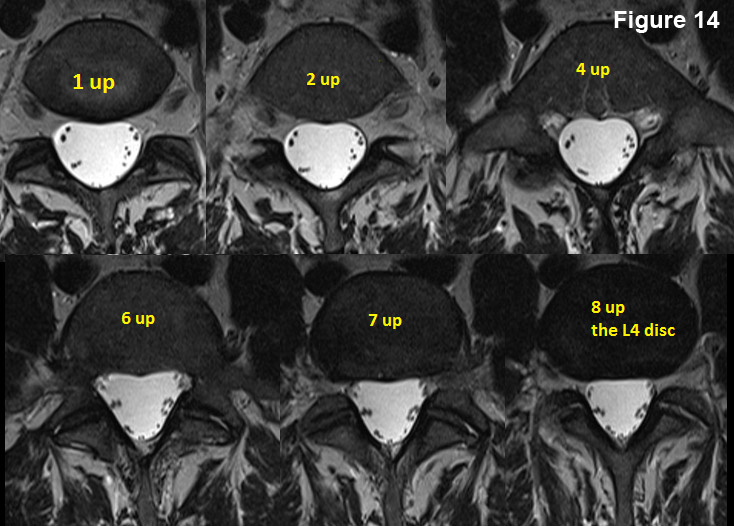

Nosotros are at the sacral base on this DVD. (effigy 13)

Now first scrolling upwardly image by image:

The first mouse click brings us to 1up, where the anatomy hasn't changed too much. The second mouse click brings u.s. to the "2 up" image, where things accept definitely changed (you can see the right facet joint now {white arrows}). The 3rd mouse click brings us to "3 up" where the anatomy continues to change (the S1 traversing roots are only starting to bud off the thecal sac on this image). With the 4th click of the mouse, nosotros take reached "iv up" which is the L5 disc. (In reality, this MRI is of such high quality, that you can really see the L5 disc on ii up, iii upwards and 4 up).

Hopefully, you now have the idea of how to work your way up the spine and by counting the discs equally you go up, y'all will always know where y'all are.

Even so having problem? I will go upwardly one more level for you, and the rest of the fashion you're on your own.

up to L4One more mouse click brings y'all above the L5 disc onto the L5 vertebral body (1 up).

Another mouse click brings you to "2 up".

Two more mouse clicks brings you to "iv up."

Another ii mouse clicks brings you up to "6 up." Some other mouse click brings y'all up to "seven up."

And finally, one more mouse click brings you upwards to the "8 upwards" image of the L4 disc. Annotation, that it is blacker than the vertebral body. If information technology were a healthy disc, yous would see a hyperintense (white) nucleus pulposus.